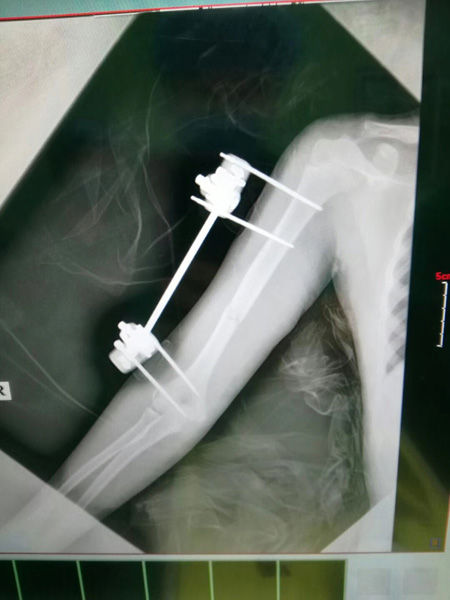

29日下午,王强赶到保定市儿童医院,他采用了当前非常先进的外固定架治疗技术,对小雪的右肱骨骨折进行了治疗,胫腓骨处则采用了克氏针进行了固定。整个手术持续了2个小时,小雪的断骨处已经恢复到了原位,手术非常成功,所有人都长出了一口气。

王利民介绍说,外固定架治疗技术的使用在保定来说还非常罕见,具有稳定性强,不用二次手术开刀留疤的优点,而王强主任正是这个领域内的全国顶尖专家,经他手术,小雪一定会尽早恢复,“这孩子的伤势比较严重,在之前,如果去北京就诊的话,她会饱受一路的颠簸之苦,更别说到了医院再排队、挂号、治疗了。现在则有了天翻地覆的变化,29日这天虽然是周末,但王强主任听到孩子的病情之后,立刻带着最先进的医疗设备来到保定,为她进行手术,真正做到了“患者不动医生动”,保定的孩子足不出户就能得到北京专家的治疗。”